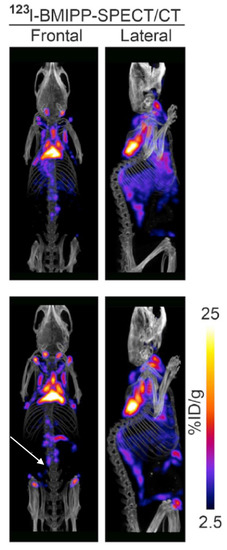

BMIPP is a fatty acid tracer routinely used for cardiac SPECT/CT in Japan [61]. It is transported into the cell by CD36 and trapped during incomplete β oxidation [62,63]. Although developed in the United States, it is not approved for clinical use by the Food and Drug Administration. Research with BMIPP likely requires on-site synthesis. However, synthesis does not require a cyclotron as the long (13 h) half-life of 123I makes it suitable for transport [64]. Additionally, 125I-labeled BMIPP produces high-resolution images on preclinical scanners and has a half-life of nearly 60 days [65]. In our hands, BMIPP identified BAT depots missed by FDG-PET/CT in mice (Figure 8) [30]. Additionally, BMIPP-SPECT/CT has a much more favorable signal-to-noise compared to FTHA-PET/CT [30]. We believe it is a measure of flux through the triglyceride pool.

Figure 8.

BMIPP-SPECT/CT with and without beta-adrenergic stimulation. BMIPP-SPECT/CT scanning for the patterns of fatty acid uptake in the metabolic active fat tissues of adult mice at room temperature after 7 days of vehicle treatment (top) or 7 days of treatment with the β3-adrenergic agonist CL-316243 (bottom row). Treatment increased uptake in classical interscapular BAT cervical depots, and inducible anterior abdominal subcutaneous (arrow) and inguinal metabolically active fat tissue. Image reproduced with permission from reference 30.